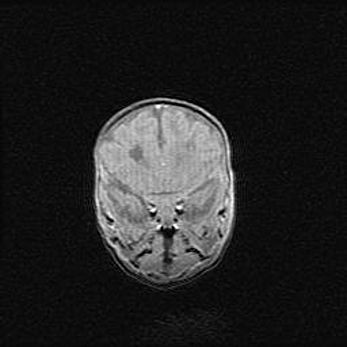

Множественные кисты обоих полушарий головного мозга, наибольшая из них в правой затылочной области. Ассиметричная атрофическая гидроцефалия.

Возраст: 7 месяцев

Вес: 5660 г

Пол: мужской

Окружность головы: 41,5 см

Срок гестации: 28-29 недель

Кисты головного мозга развиваются в результате многоочаговых некрозов вещества мозга и возникают вследствие перенесенной перинатальной инфекции, менингитов, энцефалитов, асфиксии, родовой травмы, расстройств мозгового кровообращения различного генеза. Образованию кист в веществе головного мозга плодов и новорожденных способствуют такие факторы, как высокое содержание в нем воды, недостаточная (или отсутствие) миелинизация и слабая астроглиальная реакция на повреждение.

Кисты могут сочетаться с гидроцефалией и другими поражениями головного мозга.